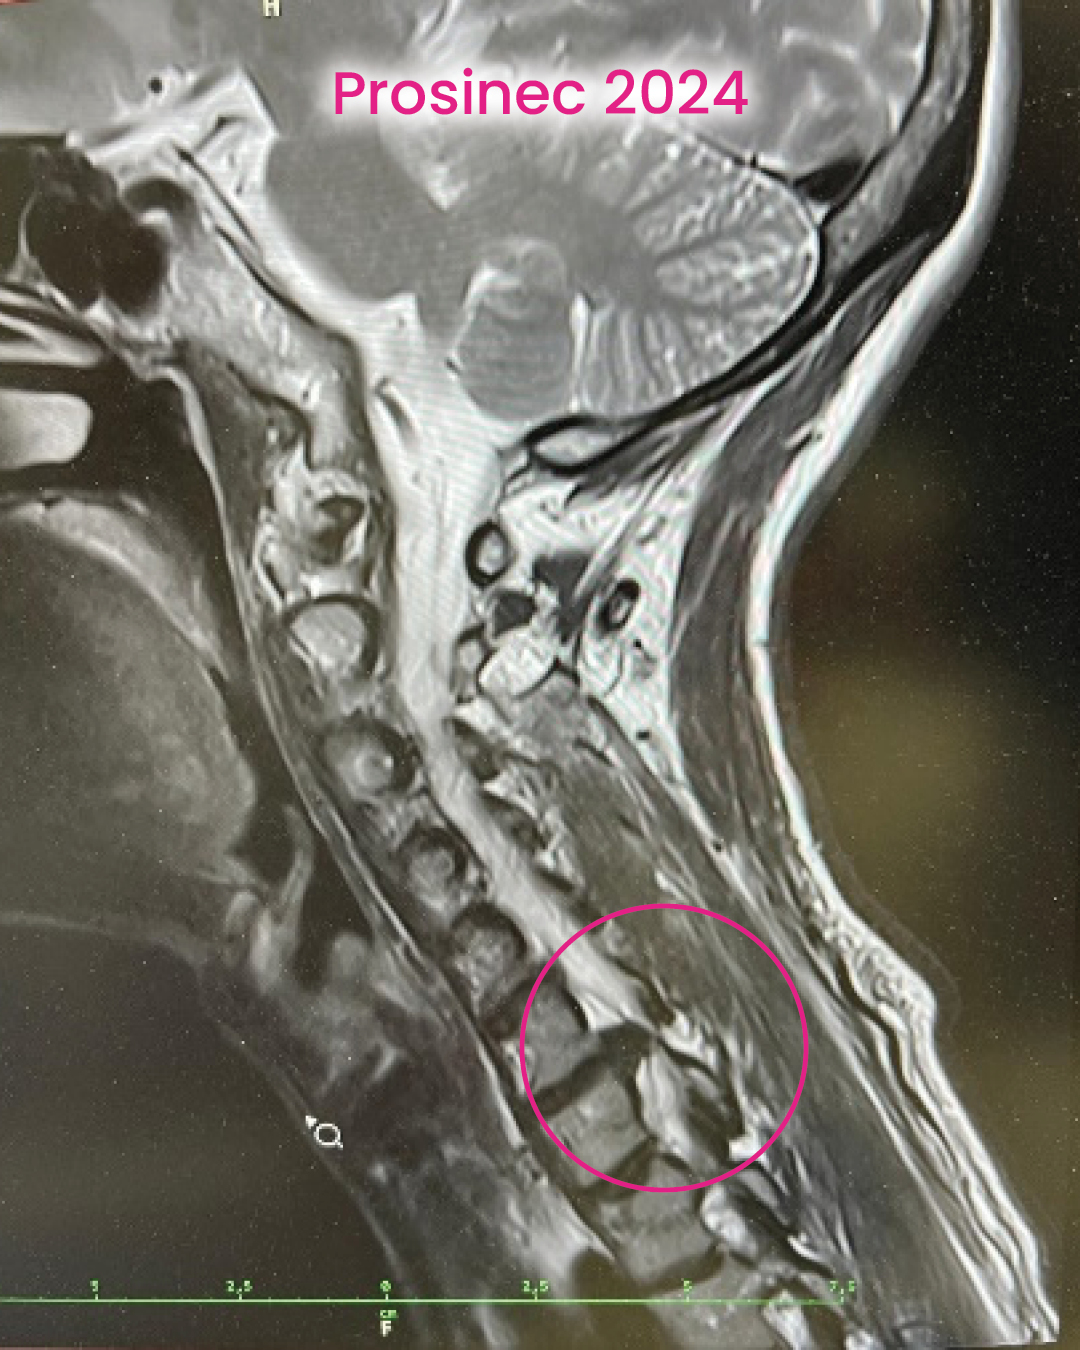

Na začátku to byl typický obraz výhřezu krční ploténky. Ploténka se posune nebo poškodí a začne tlačit na nerv. Výsledkem je kombinace bolesti, brnění a postupně i omezení funkce. Problém ale většinou není jen v samotné ploténce. Ta je spíš důsledkem toho, jak dlouhodobě funguje celé tělo.

Vstupní vyšetření tomu odpovídalo. Bylo vidět výrazné přetížení v oblasti krční páteře a celkovou nerovnováhu. Tělo nebylo schopné rozložit zátěž, takže ji kumulovalo právě tam, kde ji zvládá nejméně. Krční oblast byla přetížená, nervový systém ve vysokém napětí a problém se už promítal dál do těla. Svalová mapa ukázala totéž. Trapézy, šíje, lopatky… ale i střed těla. Tělo bylo v permanentním obranném režimu